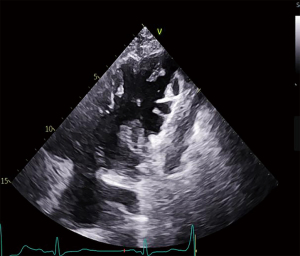

Electrocardiogram showed inverted T-waves and the Epsilon waves in leads V1–V3 (Figure 2). In view of the impaired cardiac function, we performed an echocardiogram (echo), which revealed a dilated right atrium (RA) at 59 mm × 65 mm, an expanded right ventricle (RV) at 31 mm × 37 mm with dysfunction (Figure 3A), the right ventricle outflow tract (RVOT) in parasternal short-axis view at 38 mm (Figure 3B), severe tricuspid regurgitation covering an area of 11.4 cm2, tricuspid annular plane systolic excursion (TAPSE) 13 mm and left ventricular ejection fraction (LVEF) 56% (Figure 3C). There was a pedicled mass about 26 mm × 16 mm in the apex of the RV (Figure 4A). Contrast echocardiography of the right heart was performed to define the nature of the mass, which showed that the microbubbles were not filled with the mass (Figure 4B). We also used real-time echocardiographic 3-dimensional (3D) imaging to observe the morphology of the mass (Figure 4C). Given the positive D-dimer and RA and RV dilation, we further examined the coagulation indices, arterial oxygen saturation, and lower-limb compression (through ultrasonography) to preliminarily rule out acute pulmonary embolism (PE). All the tests were negative. According to the recommendations of the European Society of Cardiology (ESC) Task Force for the diagnosis and management of acute PE (5), we considered that the patient had no predisposing factors for PE, and rather that they fulfilled the exclusion criteria for it. Based on these findings, we suspected that he was experiencing ARVC with right ventricular thrombosis, as he met 4 major criteria out of the 2010 revised Task Force criteria. The 4 major criteria for diagnosis are as follows: (I) severe dilation and dyskinesia of RV; (II) inverted T waves in leads V1–V3; (III) Epsilon wave in leads V1–V3; (IV) unsustained ventricular tachycardia of left bundle-branch morphology (6). To confirm the diagnosis, the patient underwent cardiac magnetic resonance (CMR) imaging. It was revealed that the left atrium and left ventricle were normal in morphology and function, but the RA and RV were significantly enlarged with dyskinesia. The RA was enlarged to 56 mm, the RV was enlarged to 47 mm, and the right ventricular wall was significantly thinner. The RV ejection fraction was 10%, the RV end-systolic volume was 187 mL, end-diastolic volume was 208 mL, and stroke output was 21 mL. The RV end-diastolic volume index (RVEDVI) was 115.7 mL/m2. The RV apex showed “shallow lobulated” changes with unclear demarcation from subepicardial fat, and diffuse strip-shaped abnormal enhancement shadows were observed under the endocardial wall of the right ventricular wall after delayed scanning, which was thought to be due to replacement of myocardial tissue by fibrous adipose tissue. After enhanced scanning, irregular low-signal filling defects were observed in the right ventricular apex, which was considered a sign of thrombosis. The above phenomena increased our certainty that the patient had ARVC with thrombosis (Figure 5). Since ARVC is rarely associated with thrombosis, we were interested to further study genetic relationship of this thrombosis. Unfortunately, the patient refused undergo the relevant genetic testing. We then gave the patient oral rivaroxaban 15 mg once a day as empiric anticoagulation to further confirm thrombus formation and prevent a embolic complications. Furthermore, we kept the patient on sotalol to control his arrhythmias and improve his outcome. An echo obtained 10 days later showed that the thrombus had significantly reduced to a size of 11 mm × 6 mm. This helped us to more clearly identify the presence of a thrombus, and that rivaroxaban had had a good treatment effect. Repeat echocardiography after about 4 weeks of sufficient anticoagulation indicated complete disappearance of the RV thrombus (Figure 6). Afterwards, an ICD was installed as secondary prevention of SCD.